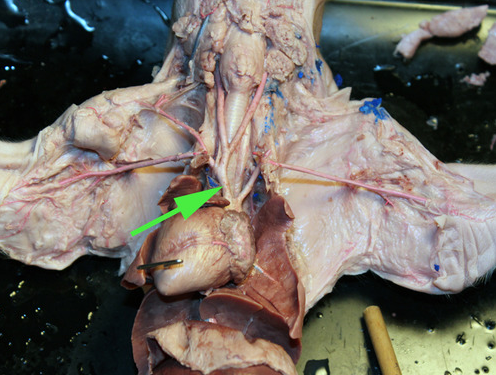

The vessel marked by the green arrow is the inferior vena cava

The vessel marked by the green arrow is the inferior vena cava